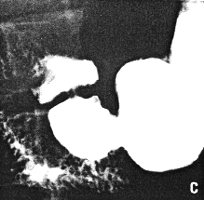

Case 35.1S.S., 67 year old male, presented with increasing dysphagia. Radiographic examination showed a constant, irregular filling defect of the lower 5.0 to 6.0 cm of the oesophagus, typical of carcinoma; it extended as far as the gastro-oesophageal junction, i.e. through the oesophageal hiatus in the diaphragm (Fig. 35.1D). The pyloric sphincteric cylinder showed a constant contraction, appearing to be "fixed" midway between maximum contraction and maximum dilatation, with absent cyclical activity (Fig. 35.1A-C). Most of the time the pyloric aperture contained barium, i.e. it was patent; at times it contained a single mucosal fold. At oesophagoscopy only the upper border of the carcinoma could be visualized; biopsy was unsuccessful. Repeat radiography a month later showed extension of the oesophageal lesion with only a trickle of barium entering the stomach.

| Fig. 35.1. A-DCase S.S. A-C Constant contraction pyloric sphincteric cylinder with absent cyclical activity. D Irregular filling defect lower oesophagus extending through diaphragmatic hiatus, indicating carcinoma. | |